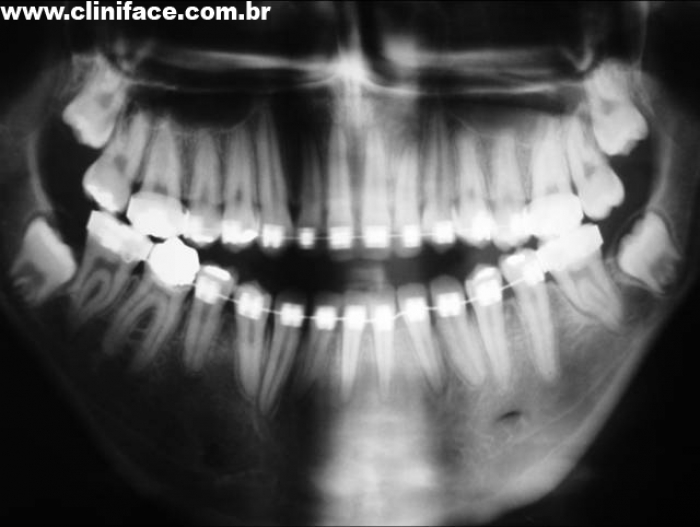

Raio x panorâmico inicial